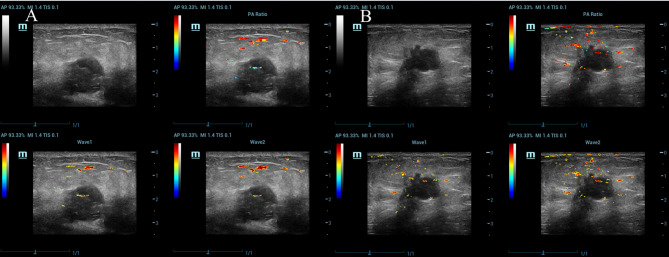

Purpose: To develop and validate a predictive model for axillary lymph node metastasis (ALNM) in breast cancer (BC) by integrating clinicopathological factors, ultrasound features, and photoacoustic imaging-derived SO2 measurements, aiming to improve diagnostic accuracy and provide comprehensive clinical insights.

Methods: A total of 317 BC patients were included, with the cohort split into a training set (70%) and a testing set (30%). Univariate and multivariate logistic regression identified key predictive factors, leading to the creation of three models: ModA (clinicopathological factors only), ModB (clinicopathological and ultrasound features), and ModC (clinicopathological, ultrasound, and SO2 measurements from photoacoustic imaging). De-Long test and ROC curve were used to evaluate and compare the diagnostic performance of the models.